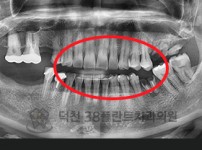

치료전후